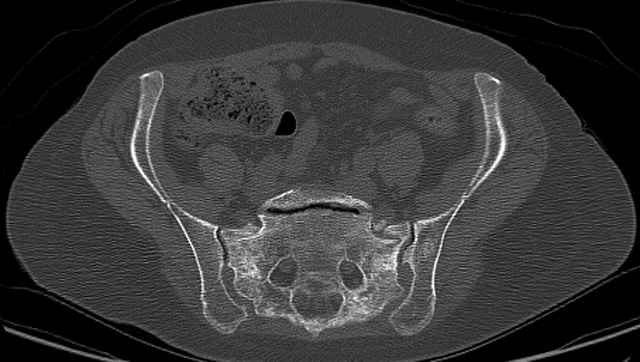

Here are a recent patient’s example slides...

3 Months After Fall

Continued Pain & Immobility

(+) Instability to Compressive Manual Exam

Pelvic CT Scan - 3 Months After Fall

Sacral Injuries

Ramus Fractures

Percutaneous Fixation

(B) Ramus-Retrograde

2 TransIliac-TransSacral

Upper Segment